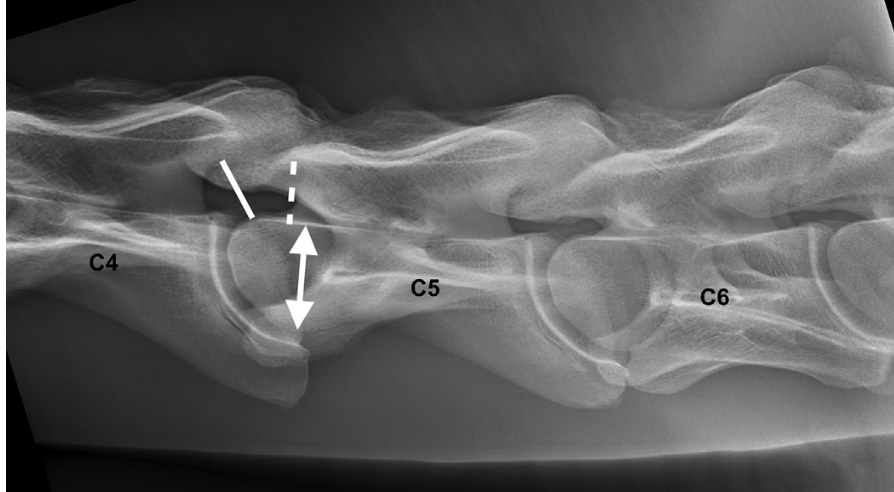

What are the types of Wobbler syndrome ?

**Type I** : affecting **young horses**, symmetric overgrowth of the articular processes (male ++, inheritance, diet, trauma, rate of growth). TB ++ **C3-C4 ; C4-C5** **Type II** : older horses, asymmetric overgrowth of one articular process, **osteoarthritic changes**. **C5-C6 ; C6-C7**